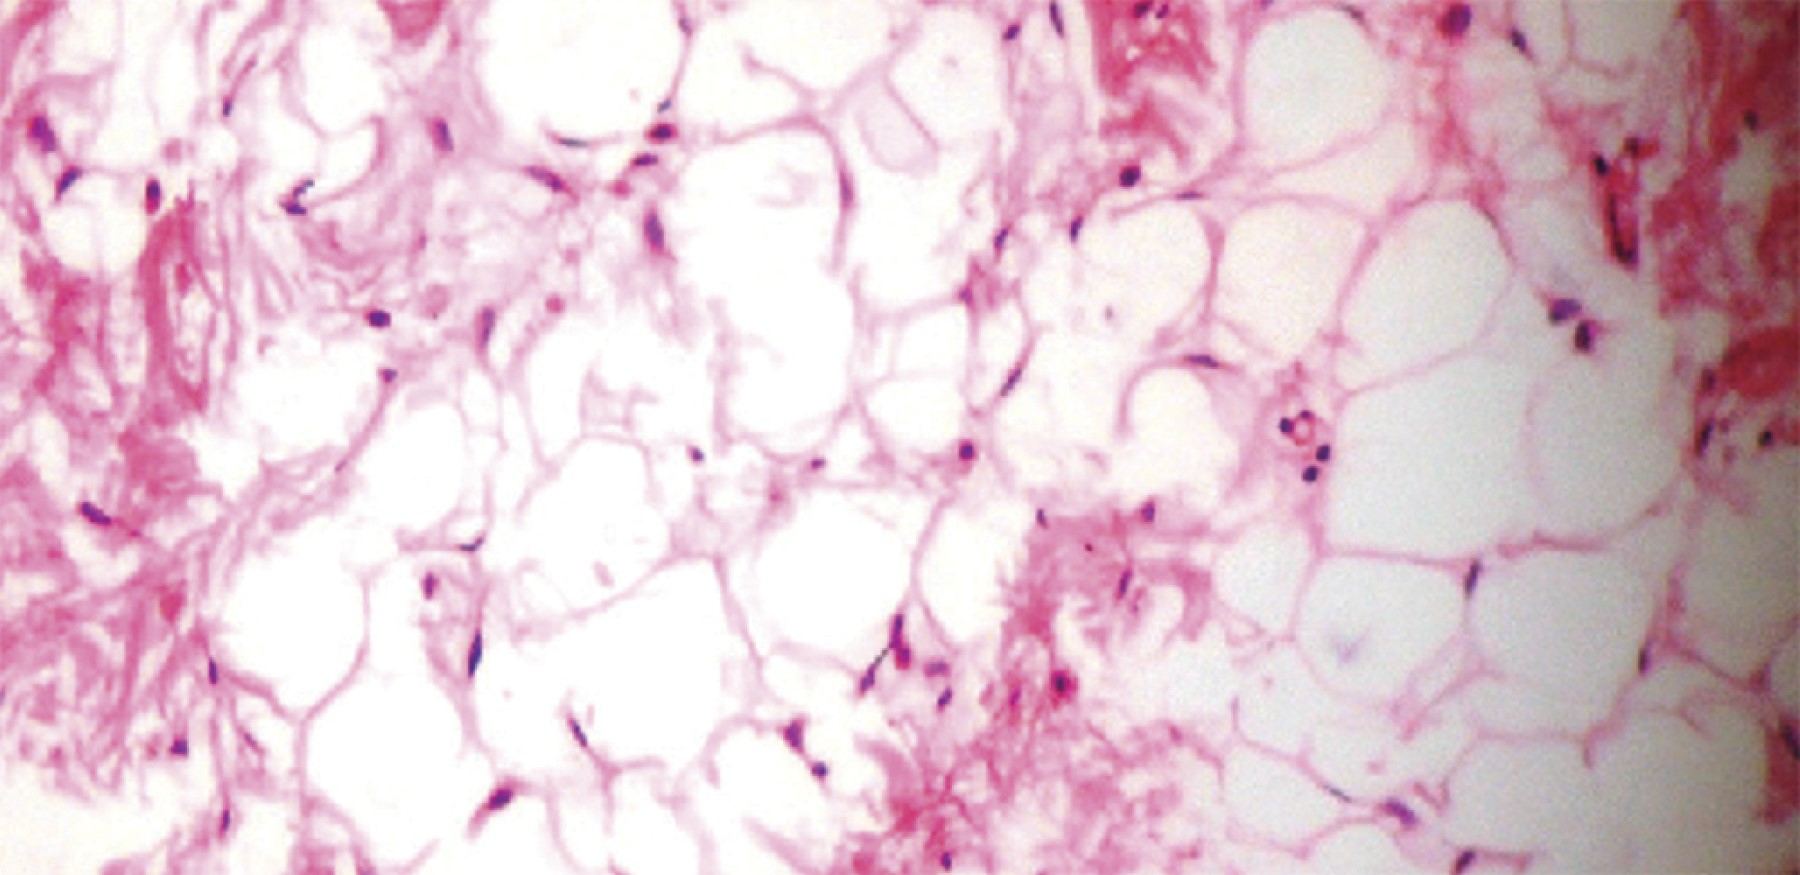

Lipofibroma of the hand is infrequent, with a mean age of presentation of 55 years. Their typical location is the thenar, hypothenar, and commissure eminences. They are usually larger than the rest of the primary soft tissue tumors when they occur in the commissure and are transferred to the dorsal compartment. They are usually not painful. The study of choice for diagnosis is magnetic resonance imaging, which shows a homogeneous image of increased intensity in T1 weighting. The types found in the hand are classic lipoma, angiolipoma, and tendon sheaths.

Figure 1